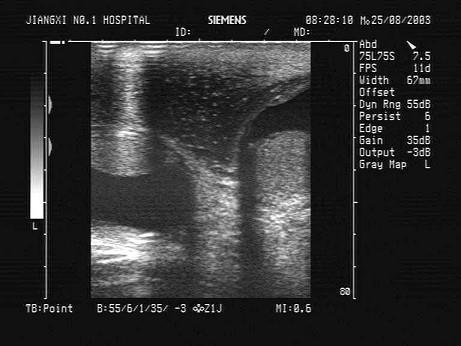

问题 男性,70岁,左下肢橡皮肿,阴囊肿大如橄榄球大小,阴囊壁增厚,B超声像图如下,患者有可能是下列哪个疾病?(?)

选项 A.丝虫病 B.华枝睾吸虫病 C.肾病综合征 D.下肢静脉曲张 E.阴囊血肿

答案 A